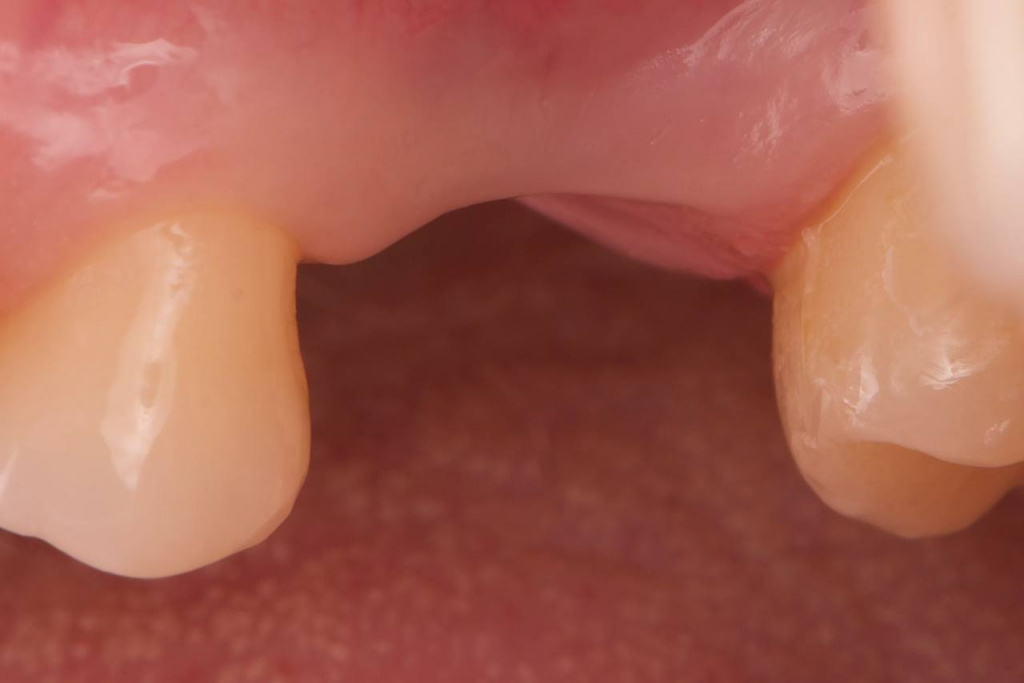

Открытый синус-лифтинг на губке и винте

Описание клинического случая:

• Открытый синус-лифтинг на губке и винте. Фиксация прямых мультиюнитов с усилием 30 Н/см

• После синус-лифтинга до установки имплантата прошло 3,5 месяца

Клинический случай Семерикова Дмитрия Юрьевича